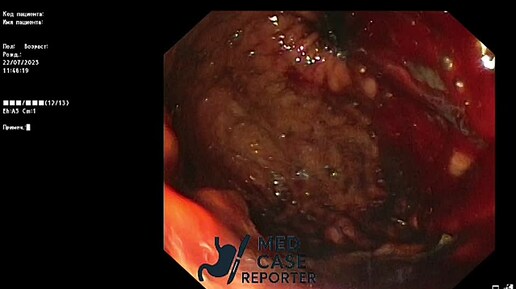

Кровотечение из разрыва Маллори–Вейса